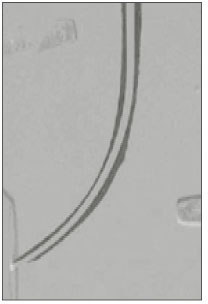

Zip/Elbow

Only one zip and elbow were created in the rotary instrumentation groups: ProFile .04 taper group(Fig. 1). There were no significant differences among the three rotary instruments, but significantly more zips and elbows were created in the K-Flexofile group(p<0.05).

Fig. 1

Composite image of the simulated root canal with apical zip and elbow in the ProFile .04 taper instrument.